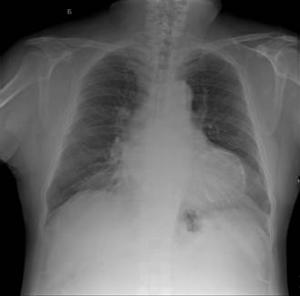

胸部X線攝片可見有沿肺段分布的均勻、濃密的實變影,多見於上葉後段、下葉背段。肺膿腫初形成時多呈圓形,內壁光滑。慢性肺膿腫時壁變厚、膿腔大小不一,小者直徑僅為1~1.5cm,大者可達13~15cm,膿腔形態不規則,大多伴有液平。血行感染常為雙側性,片狀、斑片實變影,下葉多見,可伴有膿胸或膿氣胸。